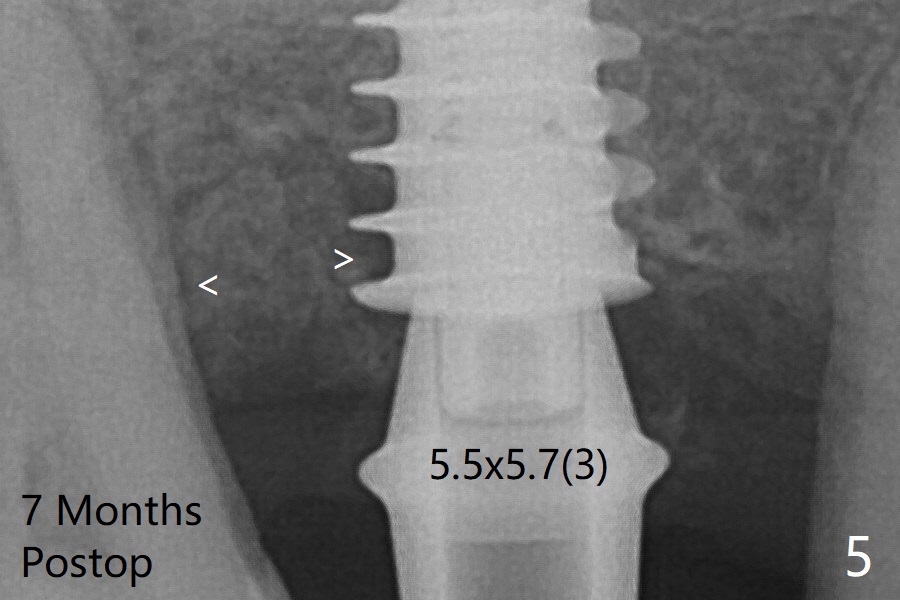

The bone graft (Fig.3 *) appears to have attached to the root of the neighboring tooth and the implant threads 7 months post op (COVID 19, Fig.5 arrowheads)).